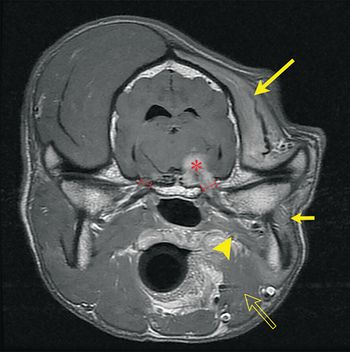

A team from UC Davis helps a border collie recover after her skull was dislocated from her spine.